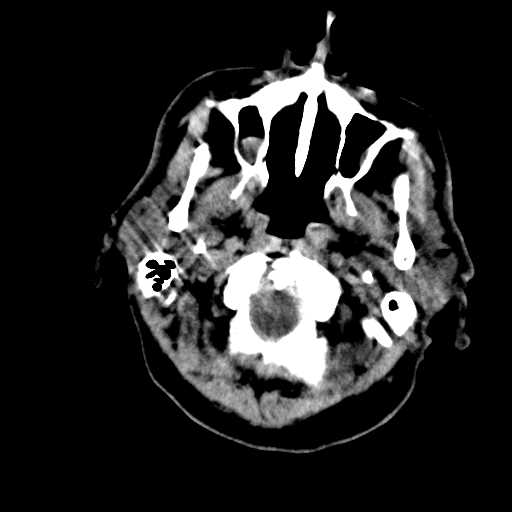

Figure 2: Examples of CT scan slices that were removed during preprocessing. These slices were eliminated because of lack of relevant brain tissue, or poor image quality, ensuring that only the most informative slices contribute to the classification process.

Slices from CT scan images that lacked relevant diagnostic information were manually removed, as illustrated in Fig. 2. This process excluded slices with missing brain tissue or poor image quality, ensuring that only the most informative and clinically relevant scans were used for classification. Following this initial filtering step, additional preprocessing was applied to further refine the dataset.